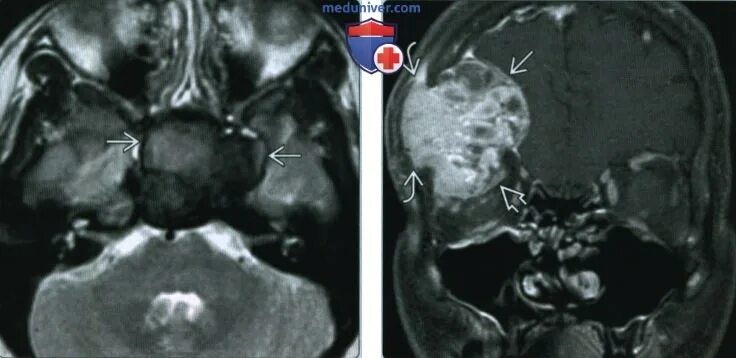

Т2 гипоинтенсивный